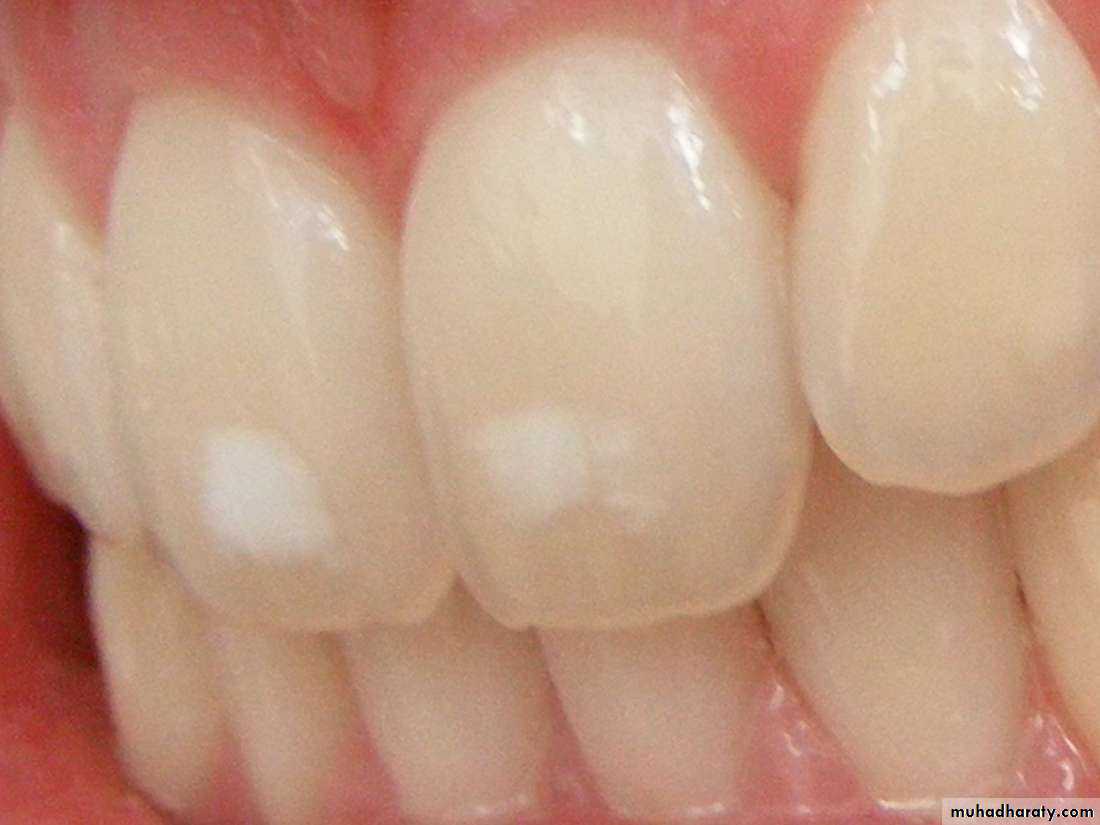

• White or chalky spots

• 5. White or chalky spots